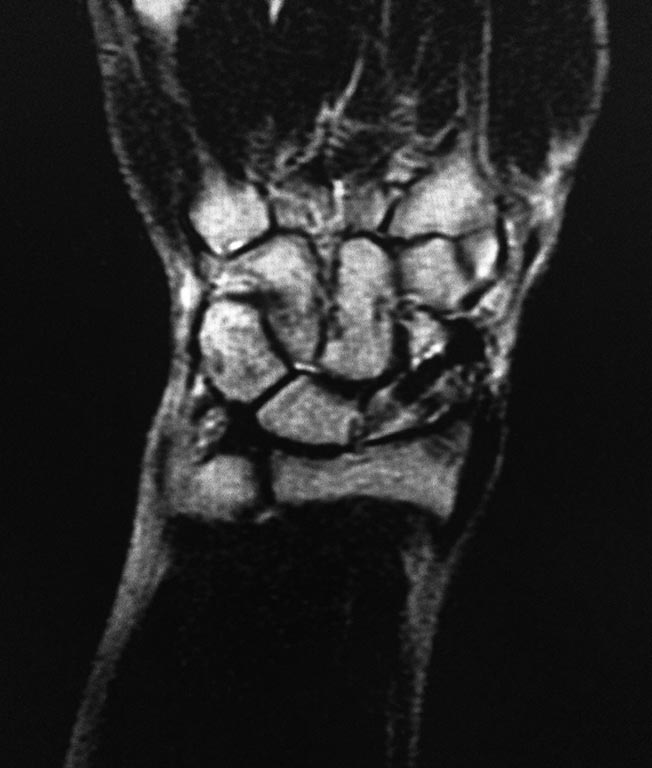

Здравствуйте. Мужчина 30 лет. Травма около 5ти лет назад, МОС винтом, в

данное время в проекции ладьевидной кости болей нет, осевая нагрузка на

1ю пястную кость безболезненная, боли беспокоят при пальпации в проекции

трехгранной кости и движениях в лучезапястном суставе (при пассивных и

активных движениях возникают острые боли, так же в проекции

трехгранной кости). На МРТ отмечаются проблемы в этой зоне. Со слов